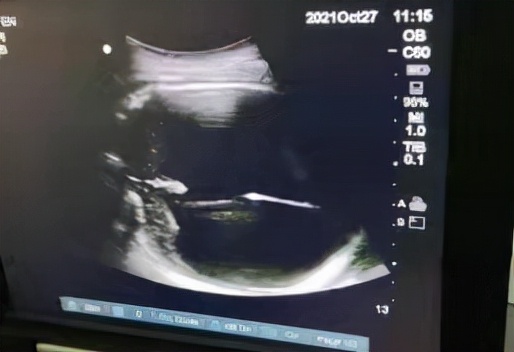

为确保手术万无一失,术前医护人员做足了“功课”。10月27日,手术正式开始,产科副主任医师赖华、住院医师祝慧婷,超声科医师、手术室护士齐聚上阵,为手术护航。超声引导下抽出脑脊液680ml。术毕,彩超检查提示胎儿双顶径为86mm,相较之前胎儿的双顶径及头围明显缩小了,这为孕妇阴道分娩创造了良好的条件。术后,给予该孕妇预防抗炎治疗,最终通过引产,该孕妇顺利阴道分娩。